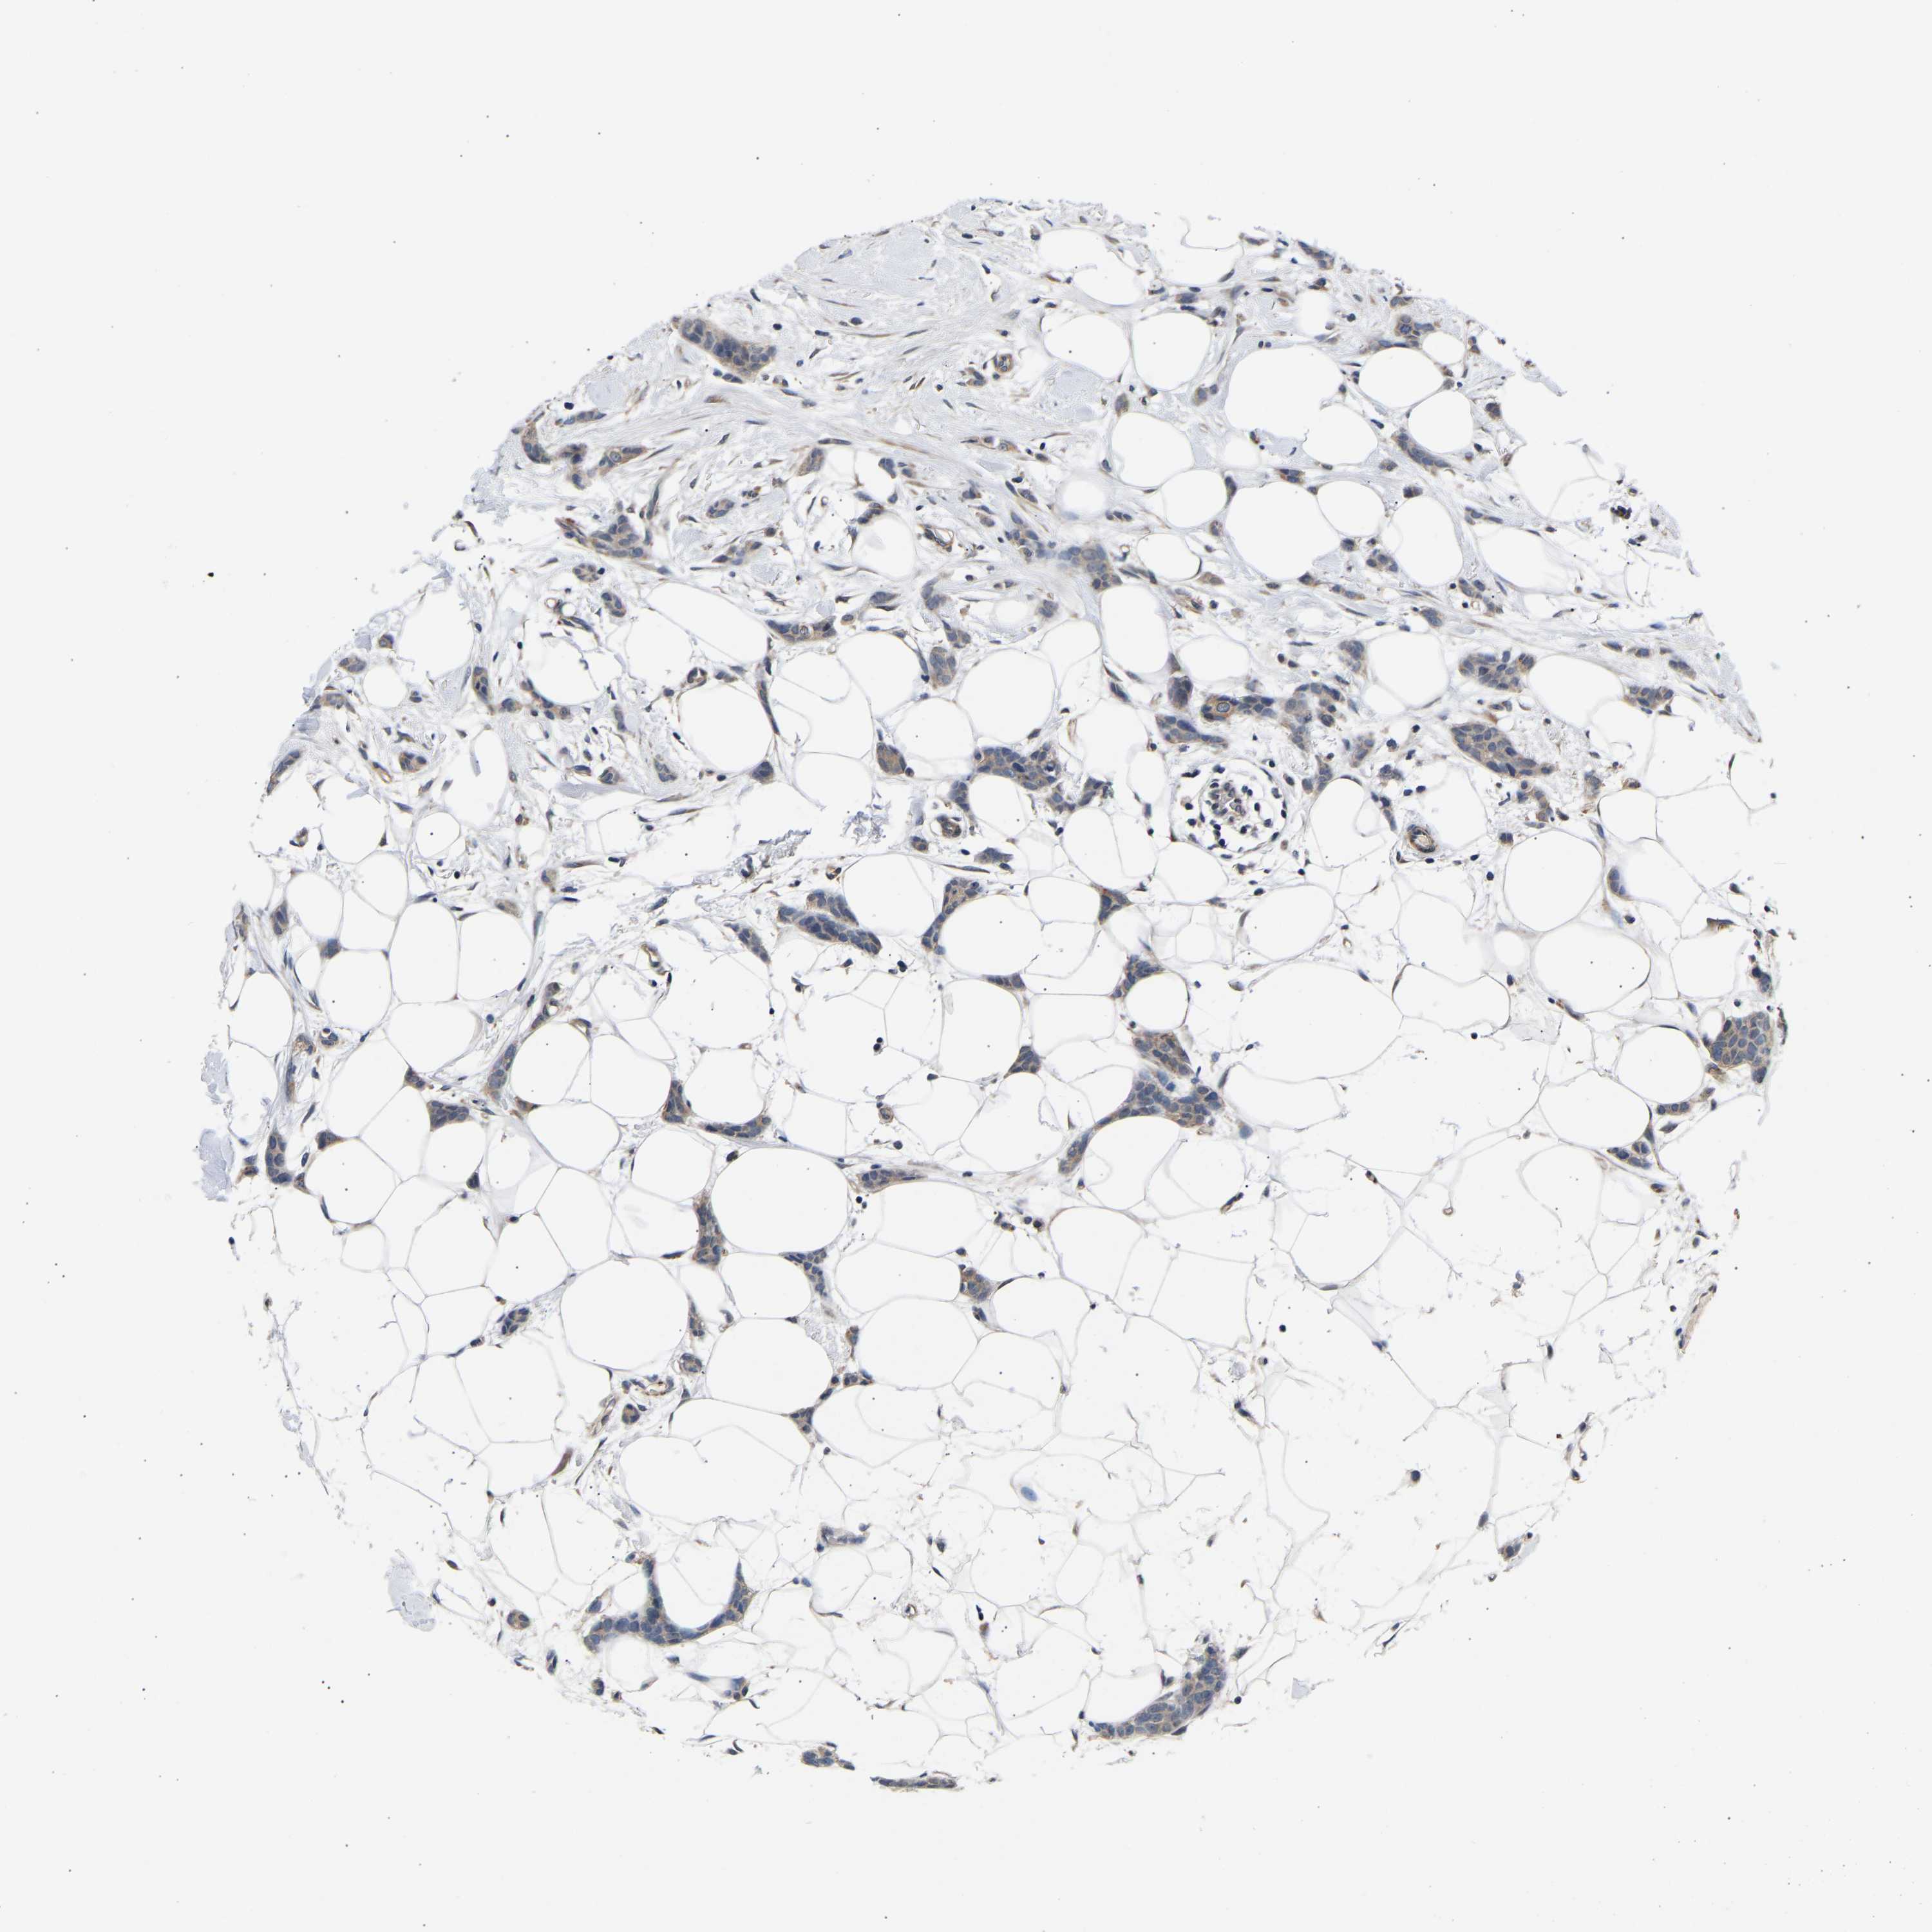

CANCER BREAST CANCER Show tissue menu

BRCA TCGA BRCA VALIDATION PROTEIN EXPRESSION